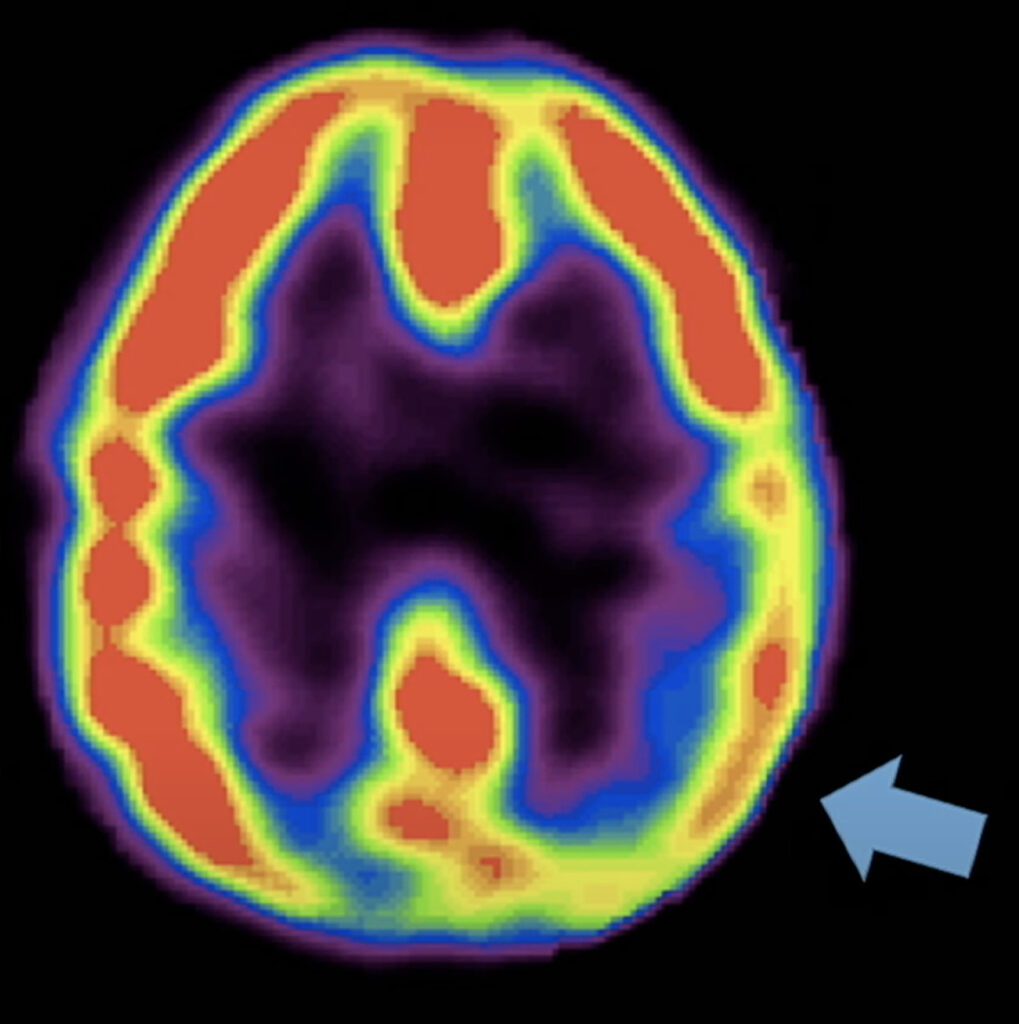

Newberg correlated fMRI brain scans with the study respondents’ descriptions of when they experienced a feeling of enlightenment or spiritual awakening during meditation. These scans showed increased blood flow and the firing of neurons in different parts of their brains. Newberg identified five core elements of the enlightenment experience.

The limbic area of the brain is the area of the brain that controls emotion. When something intense happens, this area will appear to fire up, turning red due to a rush of blood flow.

The brain scans of respondents that described this feeling of clarity showed one side of the thalamus lighting up and the other side going dark.

The thalamus is the center of the brain that takes our sensory information and constructs our view of reality.

Right behind your forehead is your frontal lobe. When you are concentrating, your frontal lobe turns on. The frontal lobe is the seat of the will. It’s what helps you make things happen. When the respondents felt a sense of surrender, the red area in their frontal lobe kind of melted away.

The brain scans of respondents that described this feeling of unity showed their parietal lobe area light up. The parietal lobe takes all of our sensory information and constructs a sense of self and our relation to the world. When you experience a profound sense of oneness and unity with the universe, the parietal lobe dims. The more it dims, the more the sense of self goes away, and the stronger the feeling of unity and oneness takes over.